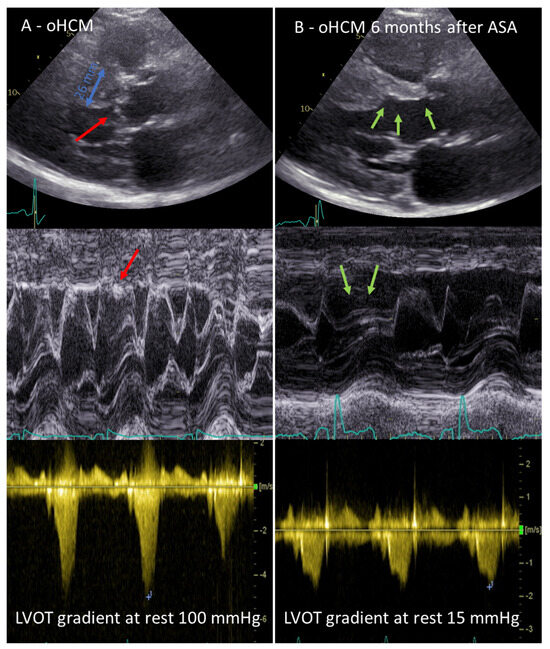

The distribution and severity of hypertrophy can vary greatly. The most common pattern is asymmetrical septum hypertrophy. About 70% of patients have obstructive HCM, with an obstruction of the left ventricular outflow tract (LVOT) or midventricular level at rest or on provocation with the Valsalva manoeuvre or exercise [7]. This dynamic obstruction at the level of the LVOT is caused by septal hypertrophy and the systolic anterior movement (SAM) of the mitral valve leaflets (Figure 1), and is largely dependent on the loading conditions and left ventricular contractility. LVOT obstruction has been shown to be an independent predictor of death related to HCM and the progression of heart failure symptoms [8].

Before proceeding to ASA, it is necessary to insert a temporary pacemaker lead into the right ventricle via the femoral or jugular vein; this step can be omitted only in patients with an implanted permanent pacemaker or cardioverter/defibrillator. The risk of a permanent complete atrioventricular (AV) block is about 10% and is caused by injury of the conduction system that is located in the immediate vicinity of the myocardial area perfused by the targeted septal branch. A transient AV block is described in up to 30% of cases; therefore, careful monitoring of the heart rhythm is necessary for at least 48 h after ASA to decide whether a pacemaker is indicated. A post-procedural echocardiogram should ideally show an LVOT gradient of <50%; not all patients show an immediate decrease in the LVOT gradient, but may show a decrease a few months after the remodelling of the infarction area [22] (Figure 1).

Figure 1. (A) Echocardiographic features of obstructive hypertrophic cardiomyopathy (oHCM; septal bulge with maximum diameter of 26 mm; red arrows indicate systolic anterior movement phenomenon of the mitral valve with contact to the septal bulge, left ventricular outflow tract [LVOT] gradient at rest of 100 mmHg); (B) Echocardiographic result 6 months after alcohol septal ablation (ASA), green arrows indicate the thinning of the basal septum, resolution of SAM and LVOT gradient at rest of 15 mmHg.